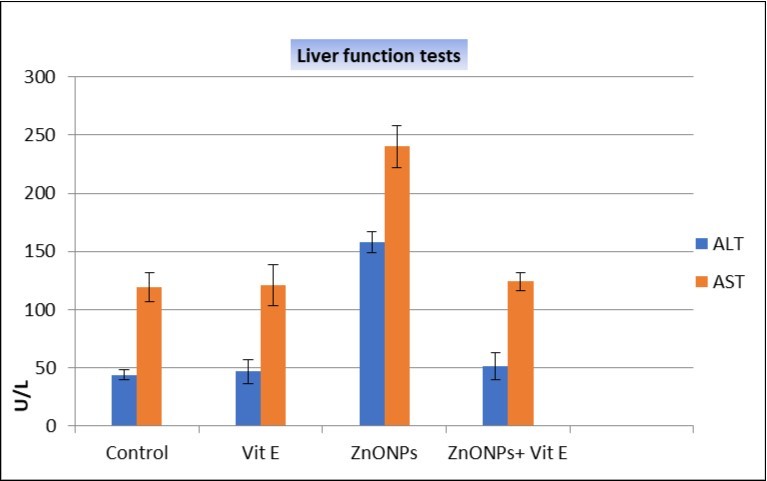

Regarding the liver enzymes, there was very significant increase in serum activities of ALT and AST (P<0.001) in the ZnONPs-treated group when compared with other groups (Table 4; Figure 13).

Table 4. Comparisons between mean values of ALT & AST in the different studied groups using ANOVA test| Groups/Parameter | Controlgroup(n=12) | VEgroup(n=12) | ZnONPsgroup(n=12) | ZnONPs+VEgroup(n=12) | F | P |

| ALT: (U/L)Mean ±SD | 44.2 ± 3.9 | 46.8 ± 10.4 | 158 ± 12.1 | 51.6 ± 8.7 | 316.19 | <0.001 |

| AST: (U/L)Mean ± SD | 119.1 ± 12.5 | 121.3 ± 17.6 | 240.1 ± 13.2 | 124.1 ± 18.2 | 154.53 | <0.001 |

Figure 13.Comparison between mean values of ALT & AST in different studied groups using ANOVA (analysis of variance) test

On the other hand, the changes in ALT and AST levels were statistically decreased in ZnONPs+VE treated group when compared with ZnONPs animals. This result is in agreement with Al-Rasheed et al. 13 who reported that VE has the ability to normalize levels of such enzymes.